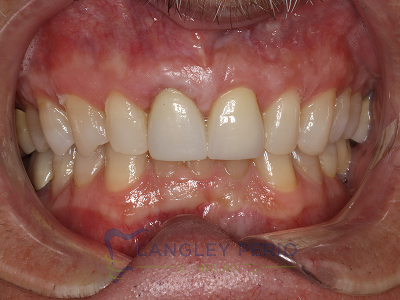

Case 1

Connective tissue grafting was performed to correct gingival clefting caused by over-aggressive toothbrushing